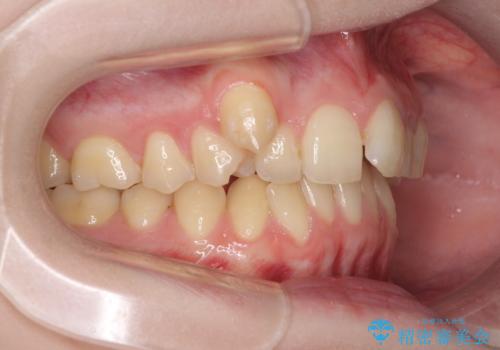

片側の八重歯であり上顎の正中がずれていたため、上顎左右第一小臼歯2本を抜歯して排列することとしました。

下顎の骨格的なズレが大きかったため、上下歯列のバランスが取れるか心配でしたが、上下ともに左右対称に近い歯列で治療を終えることができました。